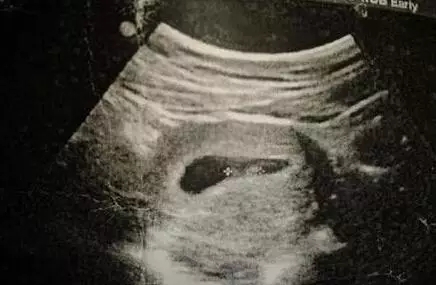

三、国外新奇小肿块原理

个别有经验的妈妈还有另一种看图方式:十一至十三周,所有的胎儿都会在双腿之间长出一个小肿块,而这个肿块的角度则会显示出它是个男孩还是女孩。据说如果小肿块翘起来30度以上就是男孩,但如果小角度就是女孩。请看下面的例子。

2017生男生女计算器

小肿块以一个陡峭的角度向上指,显示这个胎儿是个男孩。

如果你可以得到一张侧面图,那么它应该会给你提供一个很好的观察小肿块的角度。